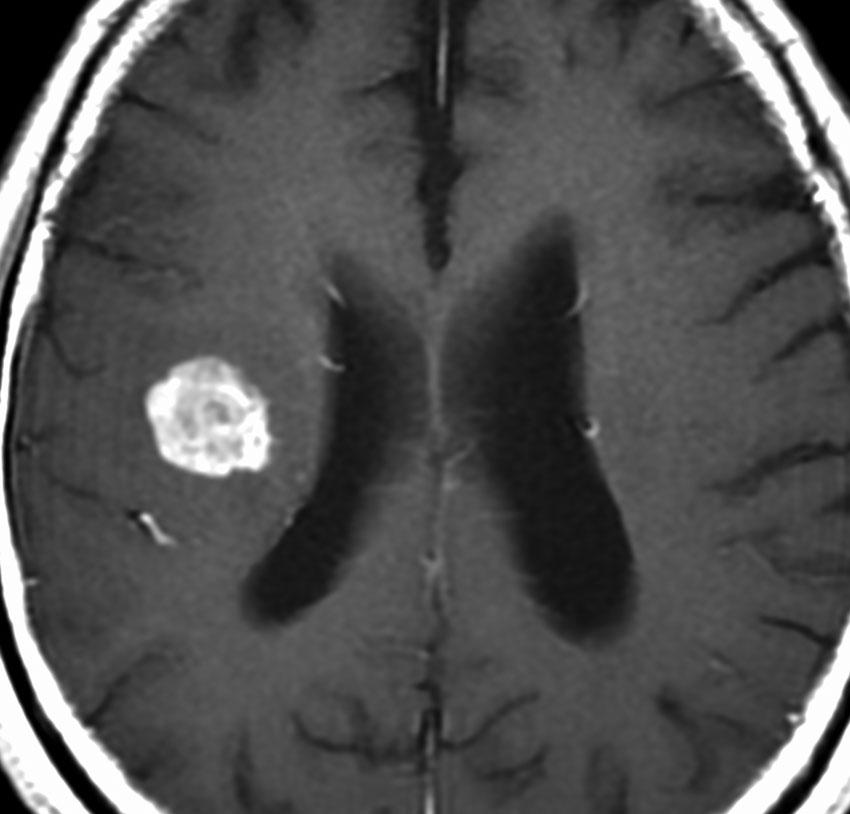

60代の患者さんの右前頭葉深部から島回に発生したものです。初発症状は症候性てんかんです。

ガドリニウム増強される腫瘍の中心部に壊死があり,悪性神経膠腫としては腫瘍周囲浮腫が強すぎるように見えるので,リンパ腫 PCNSLに似た画像所見です。

IDH1, IDH2はwild typeで変異なし,ATRX染色陽性,MIB-1 25%と高値でした。